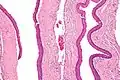

Micrograph of an odontogenic keratocyst. H&E stain.

Odontogenic keratocysts have a diagnostic histological appearance. Under the microscope, OKCs vaguely resemble keratinized squamous epithelium;[13] however, they lack rete ridges and often have an artifactual separation from their basement membrane.[2]

The fibrous wall of the cyst is usually thin and uninflamed. The epithelial lining is thin with even thickness and parakeratinised with columnar cells in the basal layer which have focal reverse polarisation (nuclei are on the opposite pole of the cell).[11] The basal cells are an indication of the odontogenic origin as they resemble pre-ameloblasts. The epithelium can separate from the wall, resulting in islands of epithelium. These can go on to form 'satellite' or 'daughter' cysts, leading to an overall multilocular cyst.[9] Presence of daughter cysts is particularly seen in those with NBCCS.[11] Inflamed cysts show hyperplastic epithelium which is no longer characteristic of OKCs and can have resemblance to radicular cysts instead. Due to areas of focal inflammation, a larger biopsy is required for correct diagnosis of odontogenic keratocysts.[9]